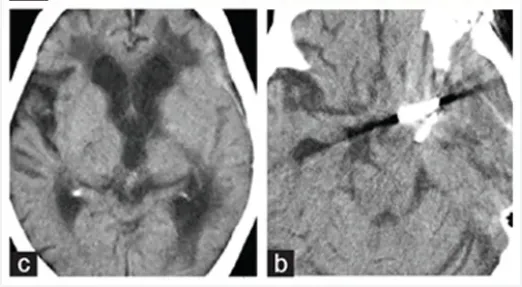

85岁妇女在一次预防性脑MRI评估中被诊断为左无症状性后交通动脉瘤。她有高血压和轻微肺气肿的病史。血管造影显示一个12毫米直径的动脉瘤起源于后交通动脉(图3a)。

由于她的年龄,医生建议她进行随访。然而,在随后的2年里,动脉瘤的直径扩大到30mm,并用含有的血栓物质压迫脑干和丘脑(图3b)。入院前5个月,临床症状发展为右侧偏瘫和左侧动眼神经麻痹。意识水平在入院前1个月下降,完全卧床不起。

当MRI显示动脉瘤病灶直径达到35mm时,转到川岛明次教授所在医院进行手术治疗(图3c)。

图3(a-c):(a)诊断4个月后的血管造影显示动脉瘤直径为12毫米,起源于后交通动脉。(b)诊断2年3个月后磁共振成像显示动脉瘤内有血栓,直径达30mm,压迫脑干。(c&d)在磁共振成像(c)和三维ct血管造影上,病灶直径扩大到35mm。6个月后(d)动脉瘤从后交通动脉向上扩张。右侧大脑后动脉未见。

图3:(a)经左外侧裂入路的手术视野。动脉瘤切除术后,动脉瘤夹闭成功,血栓被清除。动脉瘤周围未发现血管。(b&c)术后CT显示脑干解除占位效应,无缺血性病变。

病人的术后过程平安无事,无并发症,神经症状减轻。术后2周3D-CT血管造影证实动脉瘤完全夹闭,血栓完全清除(图3)。患者的神经系统状况有所改善,意识恢复到GCS15(格拉斯哥昏迷指数评分显示意识清醒),右偏瘫好转。术前完全性动眼神经麻痹部分好转。